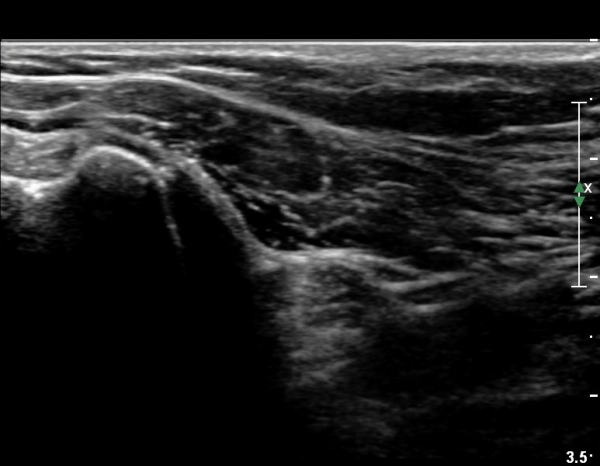

°ß°©ÇÏ±Ù°Ç ÇϺΠÁ¾´Ü¸é°Ë»ç¿¡¼­ °ß°©Çϱٰdz»  ÀÛÀº ¼®È¸È­ µ¢¾î¸®°¡ °üÂûµÈ´Ù(»çÁø 3, 4).

°ß°©ÇϱٰǠȾ´Ü¸é°Ë»ç¿¡¼­ ÇϺΠ°ß°©Çϱٰdz»  ÀÛÀº ¼®È¸È­ µ¢¾î¸®°¡ °üÂûµÈ´Ù(»çÁø 5).